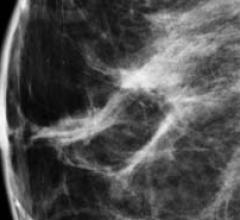

Despite decades of progress in breast imaging, one challenge continues to test even the most skilled radiologists ...